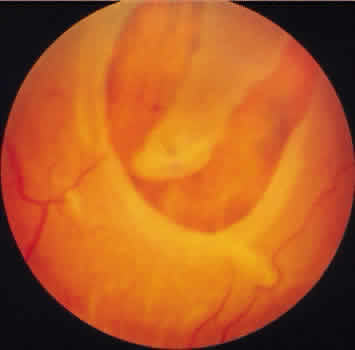

finely stippled appearance of the affected area. DEGENERATIVE RETINOSCHISIS Degenerative retinoschisis, a more extensive trophic process, presents

as a round or ovoid area of retinal splitting with a smooth fusiform elevation

of the inner layer (Fig. 17). The schisis is surrounded on all sides by typical cystoid degeneration; the

retinal pillars of the cystoid degeneration as well as the broken

pillars near the margin of the schists are prominent. Vessels are

located in the inner retinal layer, the intraretinal cavity is optically

empty, and the outer retinal layer is moderately irregular in contour.13,14  Fig. 17. Typical degenerative retinoschisis.Note extensive region of typical cystoid

degeneration with a rounded and elevated posterior margin. In the

center (arrow), radial columns are randomly disrupted, causing a disturbance in coarse

surface pattern. (× 18.) Fig. 17. Typical degenerative retinoschisis.Note extensive region of typical cystoid

degeneration with a rounded and elevated posterior margin. In the

center (arrow), radial columns are randomly disrupted, causing a disturbance in coarse

surface pattern. (× 18.)

area may extend to or somewhat posterior to the equator. On clinical examination, typical degenerative retinoschisis appears as

round or ovoid areas of retinal splitting with fusiform elevation of the

inner layer (Fig. 19). The stippled pattern of surrounding typical cystoid degeneration extends

on the inner layer for a variable distance; centrally the inner layer, which

contains the blood vessels, is thin and smooth. On contact

lens ophthalmoscopy, the inner layer is finely textured, some of the

retinal vessels are attenuated, and there is a variable number of tiny, glistening, white

dot opacities on the vitreous side. The outer layer, found

external to the optically empty cavity, is best seen with indirect

ophthalmoscopy when it becomes white on scleral depression. It is

somewhat uneven, giving an appearance of finely hammered or beaten metal. Typical

degenerative retinoschisis does not extend posteriorly to

threaten the macula, and it is not often associated with breaks in either

retinal layer; it rarely requires treatment.  Fig. 19. Clinical appearance of typical degenerative retinoschisis: diagram of involved

area and ocular fundus photographs showing optic disc, macula, and

posterior portion of schisis. Within the schisis and adjacent to

the margin is coarse stippling related to broken retinal pillars. Fig. 19. Clinical appearance of typical degenerative retinoschisis: diagram of involved

area and ocular fundus photographs showing optic disc, macula, and

posterior portion of schisis. Within the schisis and adjacent to

the margin is coarse stippling related to broken retinal pillars.